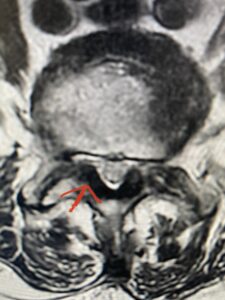

Fig 2 Axial T2-weighted lumbar MRI demonstrating severe lumbar stenosis at L4-5 secondary to thickened ligamentum flavum “knobs” (red arrow) contributing to central and lateral recess stenosis.

This 73 year-old female had a long history of low back pain and left thigh pain and heaviness of her legs when she ambulated or did activities. She failed all means of conservative treatment including epidurals and PT. On exam she had mild weakness of her left quad but otherwise was intact. Lumbar MRI (Fig 1) revealed significant L4-5 lumbar stenosis and a grade 1-2 spondylolisthesis. Her main pathology was severe, thickened “knobs” of ligamentum forming at the posterior margin of the superior facet processes of L5 and lamina (Fig 2). The patient underwent a decompressive laminectomy of L4 as well as removal of the inferior processes of L5 to widely decompress bilaterally the L4 and L5 nerve roots. Intraoperatively, the descending L5 nerve roots were compressed severely by this severe thickened ligamentum in the subarticular recess. Because of the significant spondylolisthesis we augmented her decompression with fusion. She underwent an L4-5 posterolateral fusion with segmental instrumentation (Fig 3)). Postoperatively she had an uneventful course with relief of her leg pain.